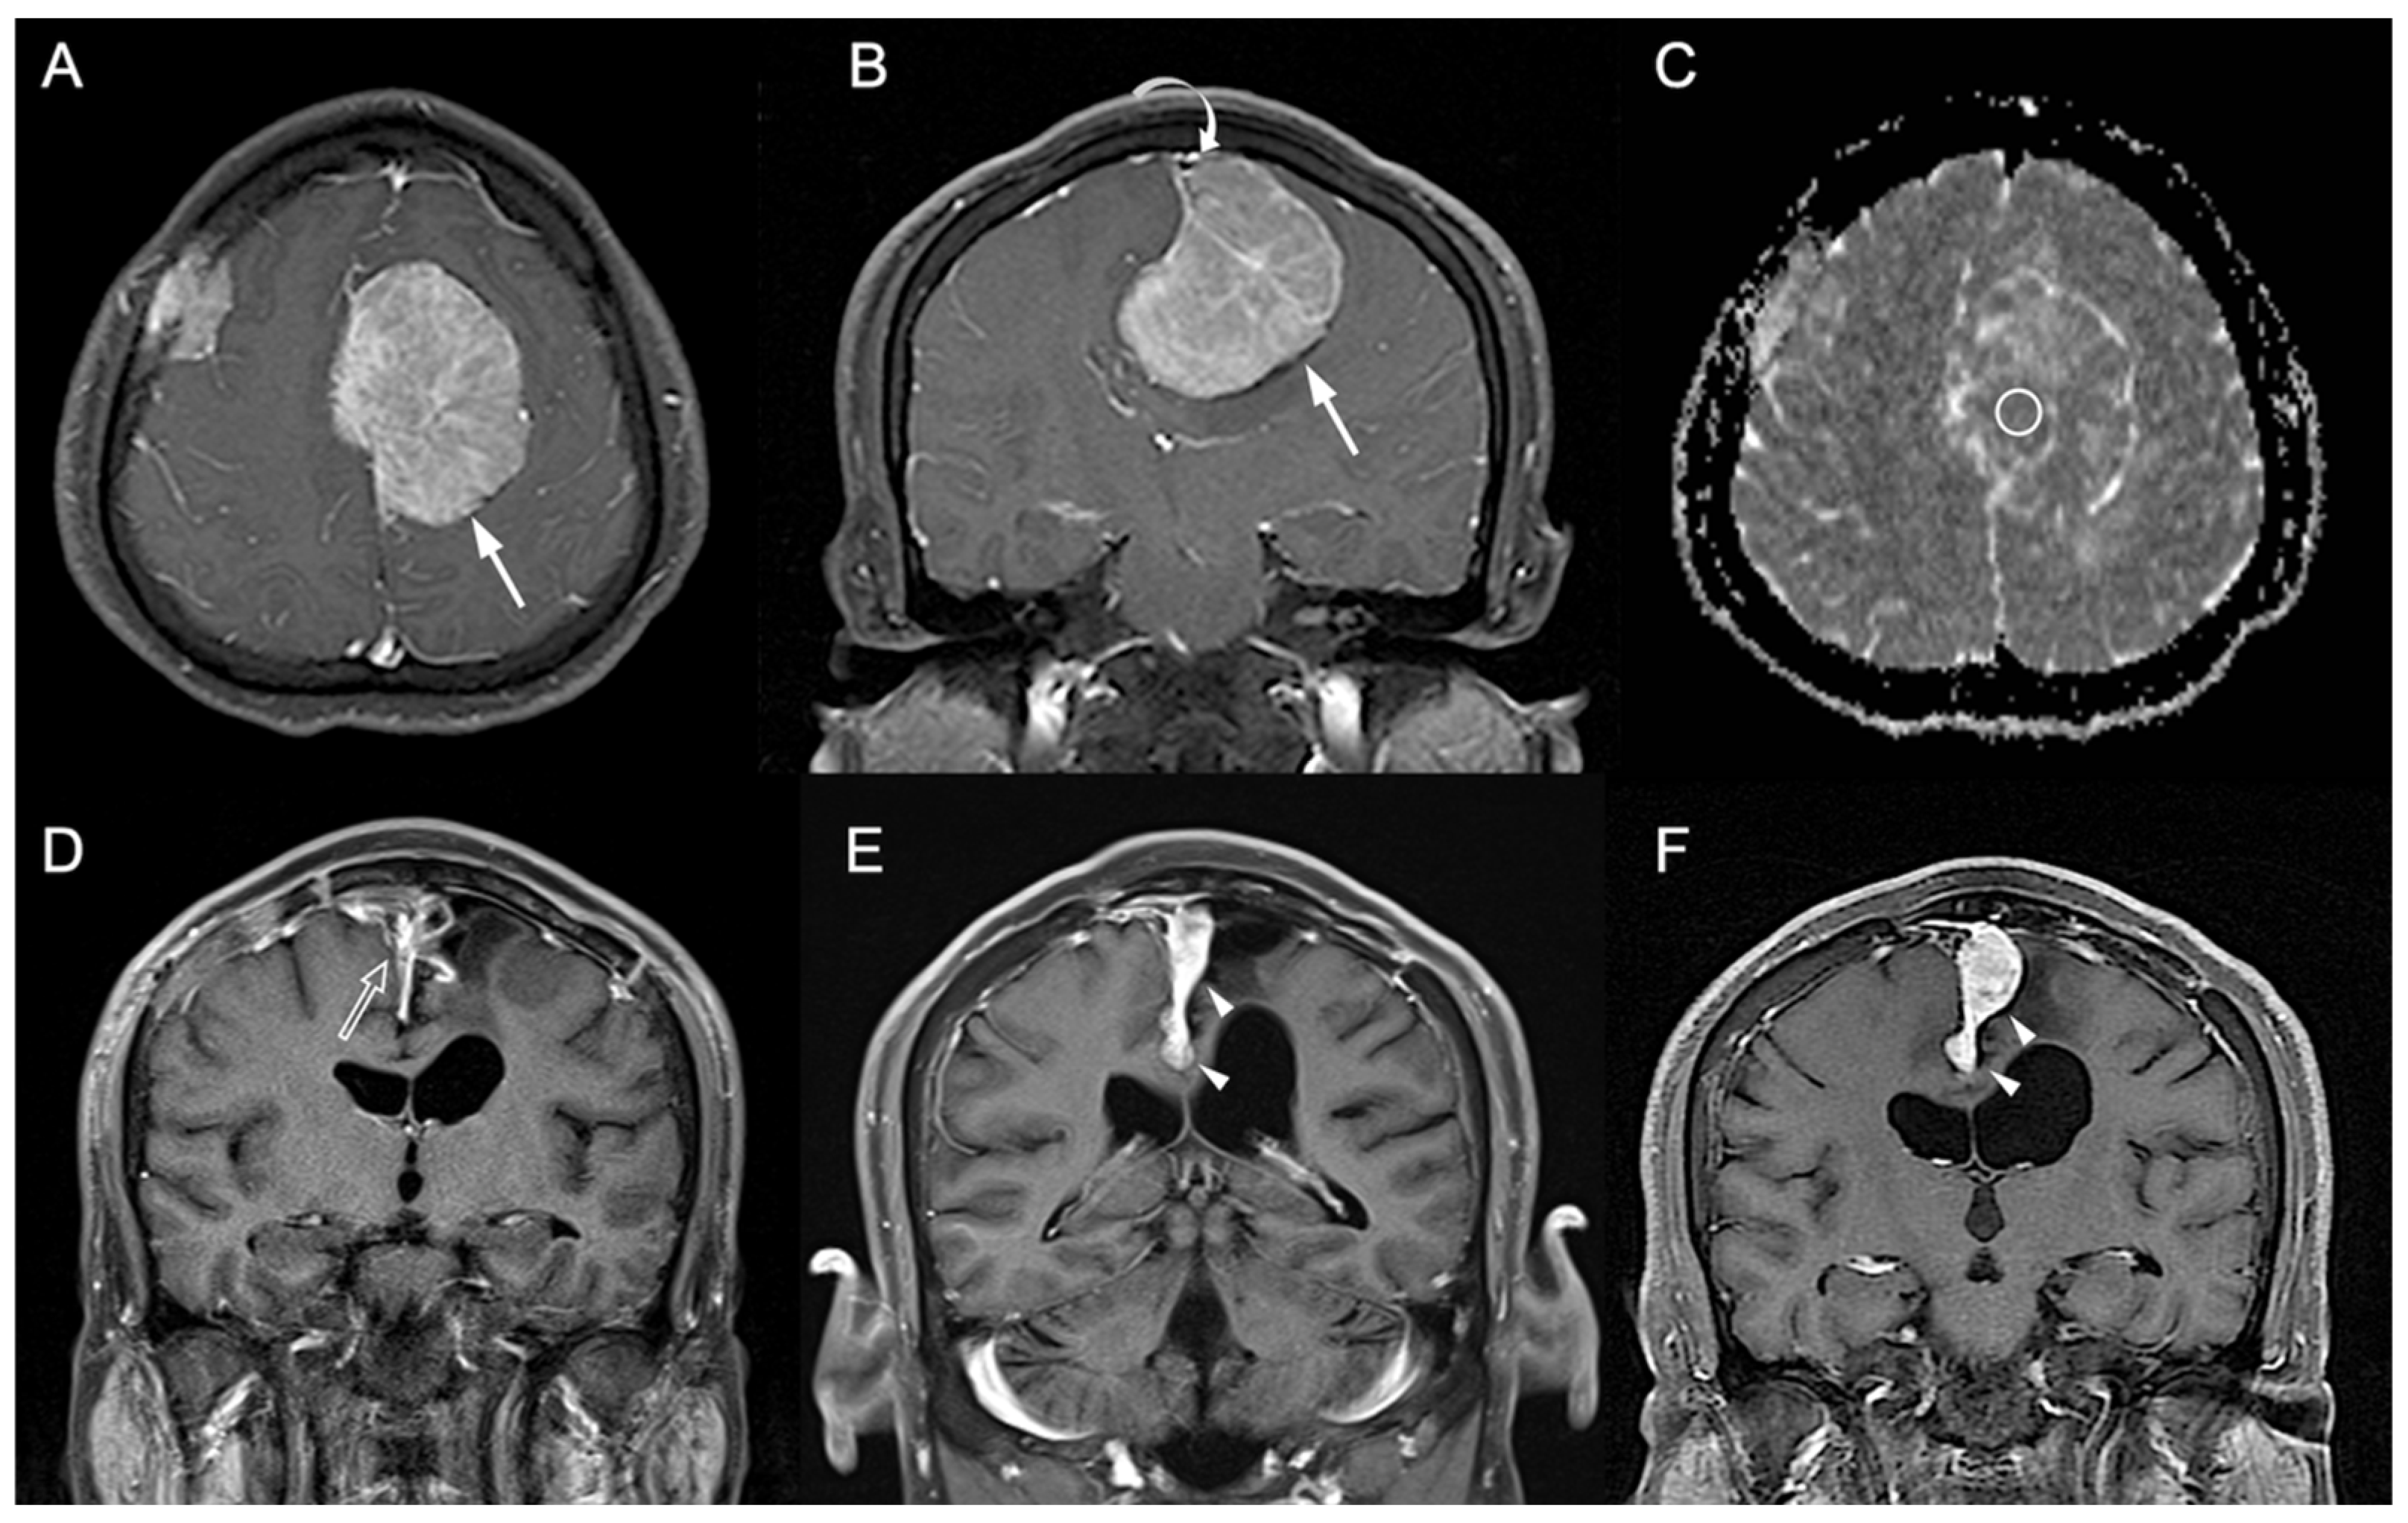

Figure 2.

A 41-year-old man with pathologically proven parasagittal meningioma (WHO grade I). (A) Axial and (B) coronal CE T1WI shows a left parasagittal enhancing tumor mass (white arrow) with invasion into left lateral recess and wall of the superior sagittal sinus (white curved arrow). The radiomic score based on the selected clinical and texture features is 0.623. (C) The measured ADC value (circular ROI) is 0.78 × 10−3 mm2/s (b = 1000 s/mm2). (D) Subtotal tumor resection is performed to preserve the superior sagittal sinus, and residual tumor (open arrow) is noted in the superior sagittal sinus. (E,F) Progressive recurrence of tumor (white arrowheads) was observed in 61 months (E) and 76 months (F) after surgery.